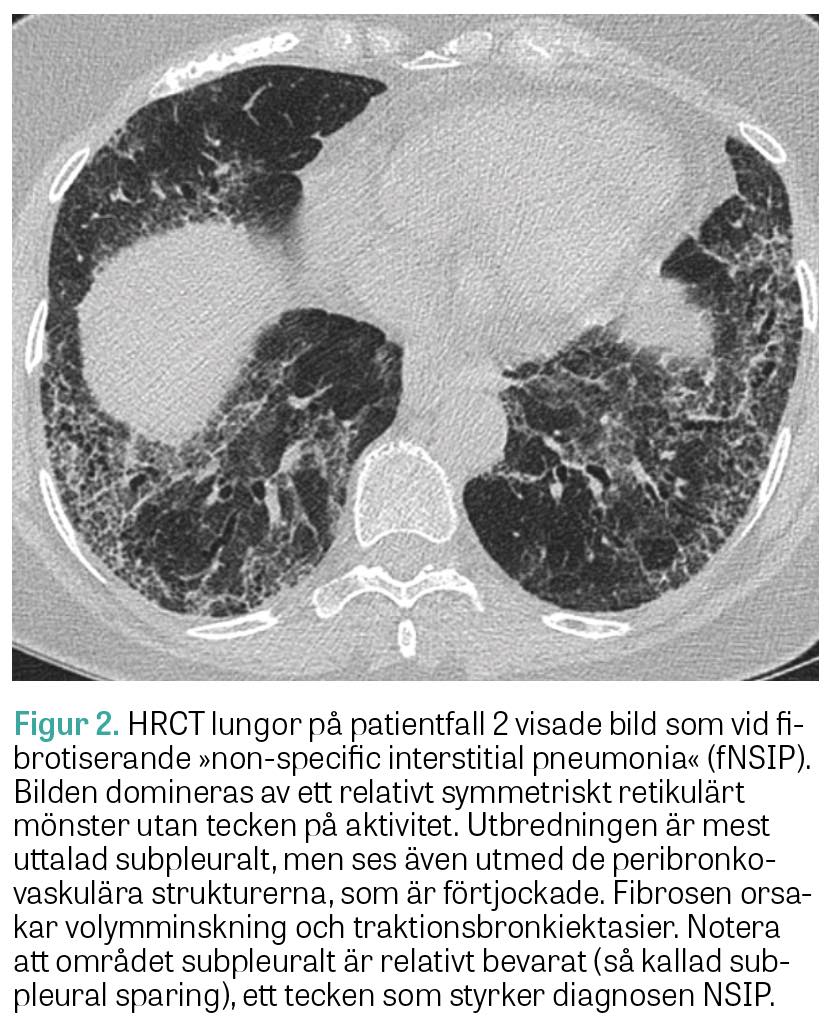

Muskelbiopsi visade histopatologisk bild med perifascikulära patologiska fynd överensstämmande med antisyntetassyndrom. EMG var normalt. MR helkropp visade utbredd inflammation i skelettmuskulatur. HRCT lungor visade mönster av fibrotisk »non-specific interstitial pneumonia« (fNSIP) (Figur 1a). Spirometriundersökningen visade markerad restriktiv lungfunktionsnedsättning: TLC 60 procent, DLCO 49 procent och FVC 52 procent av förväntad funktion.

Två år efter symtomdebut kunde diagnosen ­anti­-Jo-1-positivt antisyntetassyndrom med muskel- och lungengangemang ställas. Patienten behandlades med metylprednisolon (500 mg × 1) i 3 dagar, följt av prednisolon (50 mg × 1) och mykofenolat­mofetil (1 g × 2), samt 2 infusioner intravenöst med rituximab (1 000 mg). Vid uppföljning ett år senare hade patienten förbättrats kliniskt, men spirometri visade oförändrad bild med TLC 63 procent, DLCO 53 procent och FVC 60 procent av förväntad funktion. HRCT lungor visade en minskning av både fibrosen och den inflammatoriska aktiviteten (Figur 1b).

Figur 1.